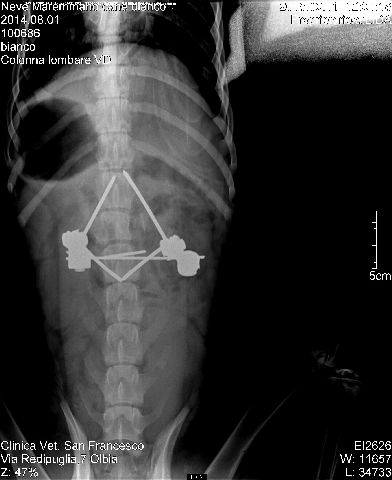

Si presenta in stato di shock post traumatico, è evidente da subito una paraparesi posteriore con assenza di dolore profondo e frattura multipla della mandibola.

Subito stabilizzato la mattina seguente attraverso rx si ha diagnosi di frattura della seconda vertebra lombare con dislocazione della colonna. Persiste l'assenza del dolore profondo>.